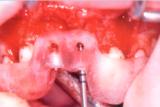

1- 3D Görüntüleme ve implant yerleştirme planlaması

2- Hastaya Özel delme klavuzu SLA ile imal edilmiş ve damak modeli üzerine oturtulmuş

3- Kesit: Çene kemiğine klavuz ile delme. Kırmızı renkle gösterilen parça, hastaya özel yapılmış olan delme klavuzudur.

-1-

-2-

-3-

Opersayon öncesi

Delme klavuzları yerleştirilmiş

Delme işlemi